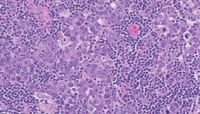

Figure 1: H&E in Germinotropic Lymphoproliferative Disorder

Low power images showing scattered variably expanded follicles with mottled nodular germinal centers while other areas (image on top right) show regressed germinal center as may be seen in hyaline vascular Castleman disease.

High power images of expanded follicles showing replacement by large plasmablastic cells with prominent nucleoli within the germinal centers.